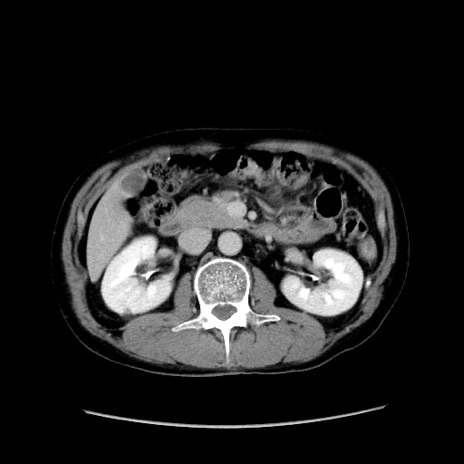

症例37(横断像)

【症例】40歳代 男性

【主訴】腹痛

【現病歴】4時間ほど前に電車に乗車中に臍部上より腹痛出現。徐々に増悪し起立困難となり、救急外来受診。生ものは数日食べていない。今朝お雑煮を食べた。

【身体所見】BT 36.8℃、BP 117/84mmHg、HR 91/min、SpO2 97%、苦悶様、腹部:臍上部広範囲圧痛あり、反跳痛±

【データ】WBC 8100、CRP 0.03